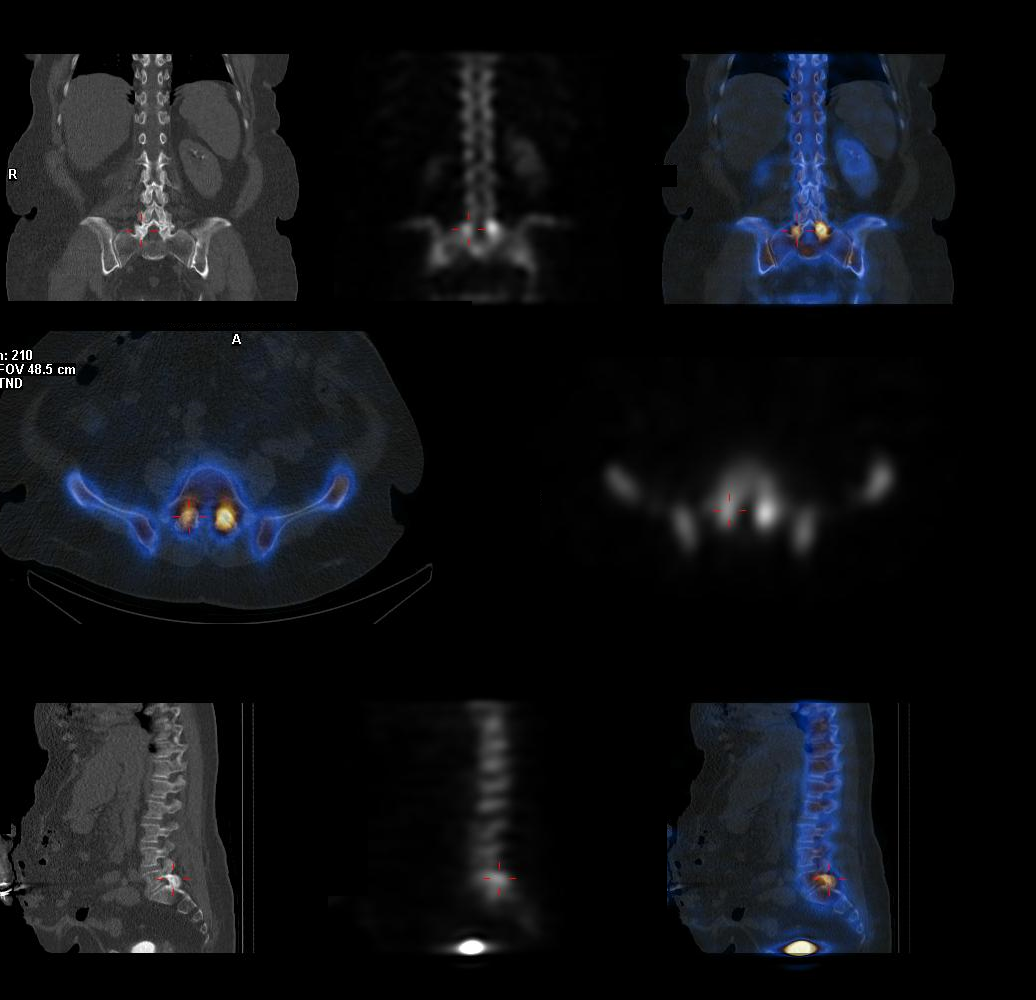

What Is Pet In Nuclear Medicine . Nuclear medicine uses small and safe amounts of radioactive material, called radiotracers, given through an iv. Positron emission tomography, also called pet imaging or a pet scan, is a type of nuclear medicine imaging. A pet scan is a type of nuclear medicine imaging. Nuclear medicine uses small amounts of radioactive material called. Positron emission tomography, also called pet imaging or a pet scan, is a type of nuclear medicine imaging. Used mostly in patients with brain or. Positron emission tomography/computerized tomography (pet/ct) is an imaging test that produces high resolution. Pet is a type of nuclear medicine procedure that measures metabolic activity of the cells of body tissues.

Positron emission tomography, also called pet imaging or a pet scan, is a type of nuclear medicine imaging. Positron emission tomography, also called pet imaging or a pet scan, is a type of nuclear medicine imaging. A pet scan is a type of nuclear medicine imaging. Nuclear medicine uses small and safe amounts of radioactive material, called radiotracers, given through an iv. Positron emission tomography/computerized tomography (pet/ct) is an imaging test that produces high resolution. Used mostly in patients with brain or. Pet is a type of nuclear medicine procedure that measures metabolic activity of the cells of body tissues. Nuclear medicine uses small amounts of radioactive material called.

What Is Pet In Nuclear Medicine Pet is a type of nuclear medicine procedure that measures metabolic activity of the cells of body tissues. Positron emission tomography, also called pet imaging or a pet scan, is a type of nuclear medicine imaging. Positron emission tomography, also called pet imaging or a pet scan, is a type of nuclear medicine imaging. Pet is a type of nuclear medicine procedure that measures metabolic activity of the cells of body tissues. Used mostly in patients with brain or. Nuclear medicine uses small amounts of radioactive material called. Positron emission tomography/computerized tomography (pet/ct) is an imaging test that produces high resolution. Nuclear medicine uses small and safe amounts of radioactive material, called radiotracers, given through an iv. A pet scan is a type of nuclear medicine imaging.